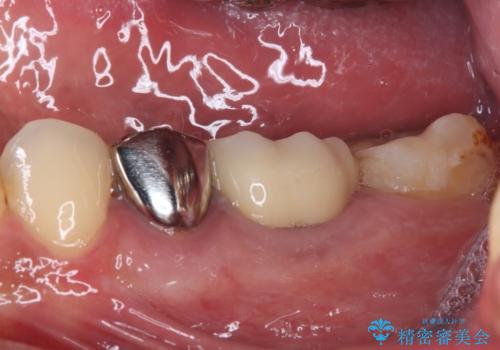

- 下顎左右の奥歯を治療途中で放置してしまっているとのことで来院された患者様です。

欠損部はインプラントによる補綴治療を、土台の外れてしまった歯は、根管治療を行った上で、補綴治療を行うこととしました。